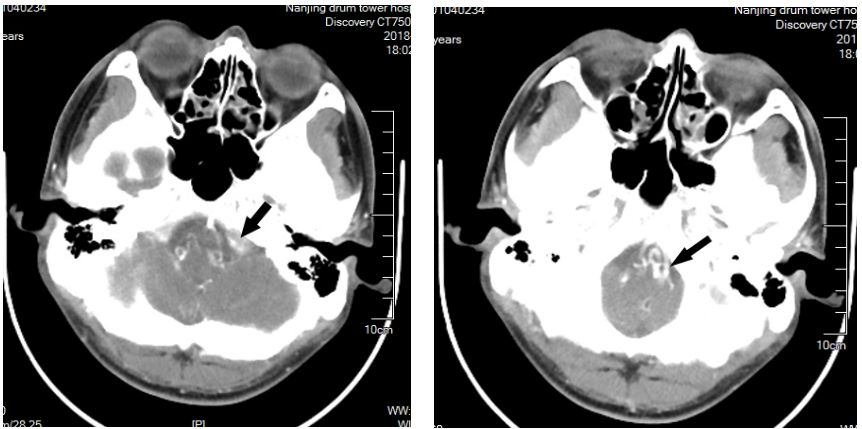

头颅MRA未见颅内异常血管,但头颅MRI-TOF像可见左侧天幕缘异常血管影(图2),CT薄层增强扫描见枕骨大孔区异常血管影(图3)。于2017年12月25日局麻下行全脑及全脊髓血管造影,脊髓血管造影未见异常,双侧椎动脉造影未见异常,最后行左侧颈内动脉造影示脑膜垂体干供血的天幕区硬脑膜动静脉瘘,瘘口位于岩骨中内1/3,直接经桥脑中脑侧静脉、扩张的延髓周围静脉向脊髓前静脉引流(图4)。造影诊断:左侧天幕区硬脑膜动静脉瘘。

图3. CTA见枕骨大孔区异常血管(箭头所示)